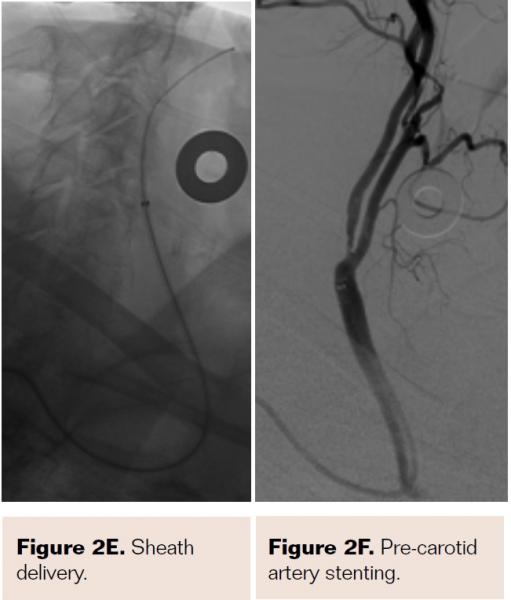

Pretreatment with dual-antiplatelet therapy (DAPT) was started 4 days prior to the procedure with aspirin and clopidogrel, with 600 mg loading dose of clopidogrel and 80 mg dose of atorvastatin the morning of the procedure. The right radial artery was accessed with a 6 Fr Terumo radial sheath, but intraarterial nitroglycerin was not administered due to a prior history of profound hypotension with sublingual nitroglycerin. Verapamil was withheld due to a systolic blood pressure of 130 mm Hg. Both right and left anterior oblique arch aortograms with a 5 Fr straight pigtail catheter demonstrated patency of the proximal great vessels, a type I aortic arch, and a calcified proximal right internal carotid artery (ICA) high-grade stenosis with patent right external carotid artery (ECA). The right common carotid artery (CCA) was selected with 5 Fr internal mammary (IM) diagnostic catheter that confirmed an 85% proximal right ICA stenosis. A soft-angled .035˝ Glidewire (Terumo) was advanced into the right ECA, exchanged out for an Amplatz .035˝ super-stiff wire (Boston Scientific), followed by removal of the diagnostic catheter, and radial sheath. A 6 Fr Shuttle sheath (Cook Medical) was delivered into the distal right CCA. After intracranial angiography, a NAV-6 Emboshield (Abbott Vascular) was deployed in the distal extracranial ICA, followed by predilation with a 4 x 30 mm Trek (Abbott Vascular), and deployment of a 7 x 30 mm Precise self-expanding stent (Cordis). Postdilation was performed with a 5 x 20 mm Maverick NC balloon (Boston Scientific), and then with a 6 x 20 mm Aviator balloon (Cordis) in order to then deliver the retrieval catheter. After repeat angiography confirmed an excellent result, the Shuttle was removed, and hemostasis achieved with TR band (Terumo) (Figures 2A-2R).